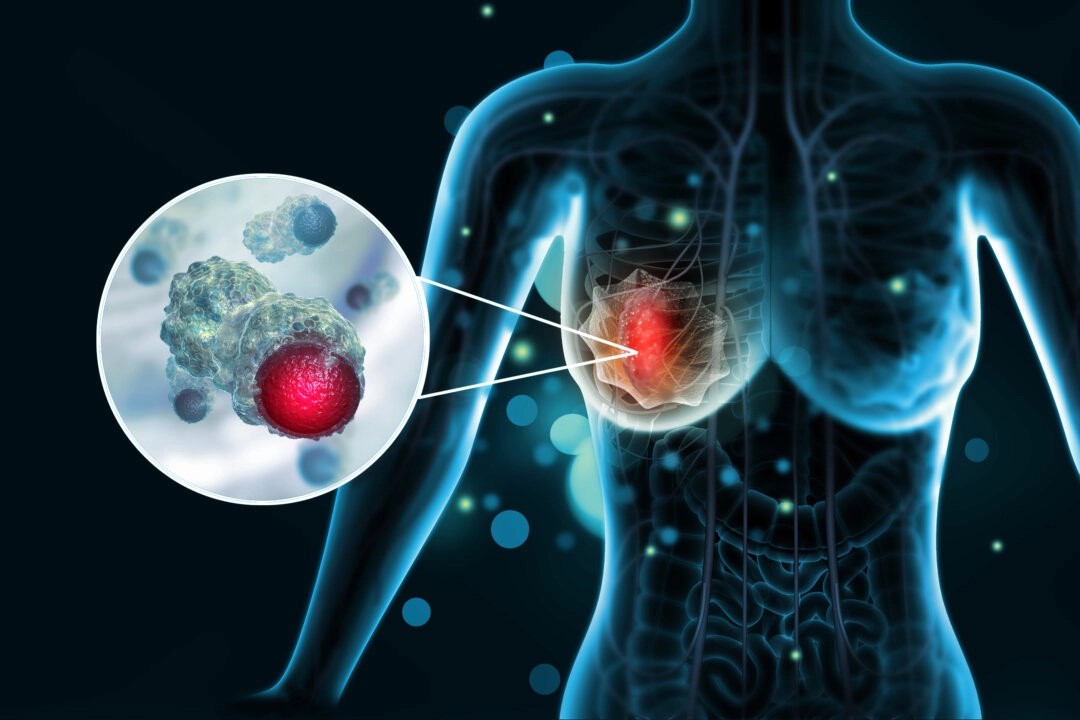

乳がんのリスクや最新の治療法、早期発見の重要性を専門医が解説。患者の体験談も交え、予防や診断のポイントを詳しく紹介します。